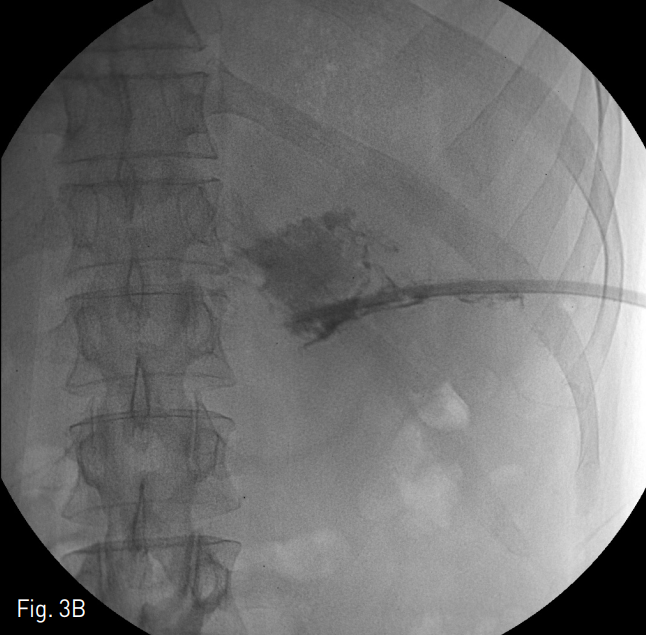

Fig. 3

The patient underwent massive saline irrigation (average total volume of normal saline: 8000cc) and aspiration necrosectomy using 50cc enema syringes. Procedure was performed eleven times in two months (A). Decreased extent of contrast accumulation at fluid cavity compared wi th ini tial fluoroscopic image (B).